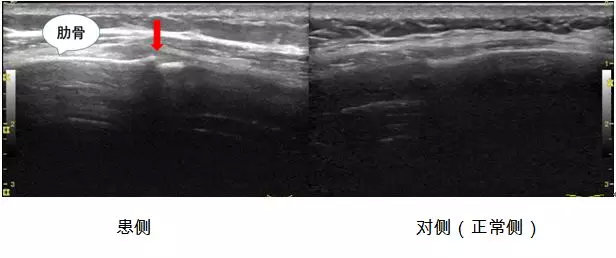

抱着试一试的态度,小王来到了北医三院超声诊断科肌骨超声门诊,超声医师接诊后根据小王描述的疼痛症状,对可疑肋骨区域进行仔细的扫查,发现了引起他持续胸部疼痛的病因:的确是肋骨骨折了,而且很明确的告知他是右侧第七前肋骨折。

因骨折端对位良好,不需要特殊治疗,可以适当使用外敷药物缓解疼痛症状,同时不宜再做剧烈运动。三个月后小王进行了超声复查,发现肋骨骨折端已完全愈合。